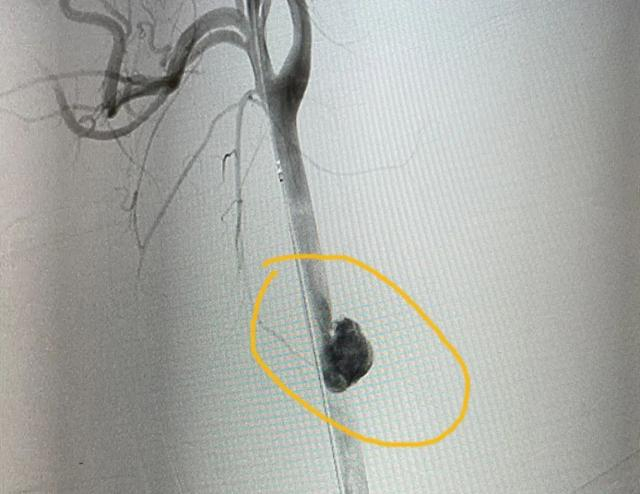

根据陈先生的病史和术前CT影像,赵文军手术团队迅速制定好了手术方案。“分两步走,先用支架从里面堵住血管破损处,再从颈部开刀进去修补血管。”

使用的支架,全称是人工血管覆膜支架,从大腿根部处通过穿刺血管置入,送到颈动脉破损处。这是介入手术范畴,需要医学影像引导,杂交手术室为患者节约救命时间的优势这时就显现出来了。

当支架在陈先生颈部顺利打开,相当于给颈动脉穿了一件“内甲”,完美堵住了出血口。

“外围血肿清除后,能看到长约1厘米的颈动脉破口,还能看到里面的人工血管覆膜支架。”赵文军说,手术视野清晰,能让外科医生更快速地完成缝合。